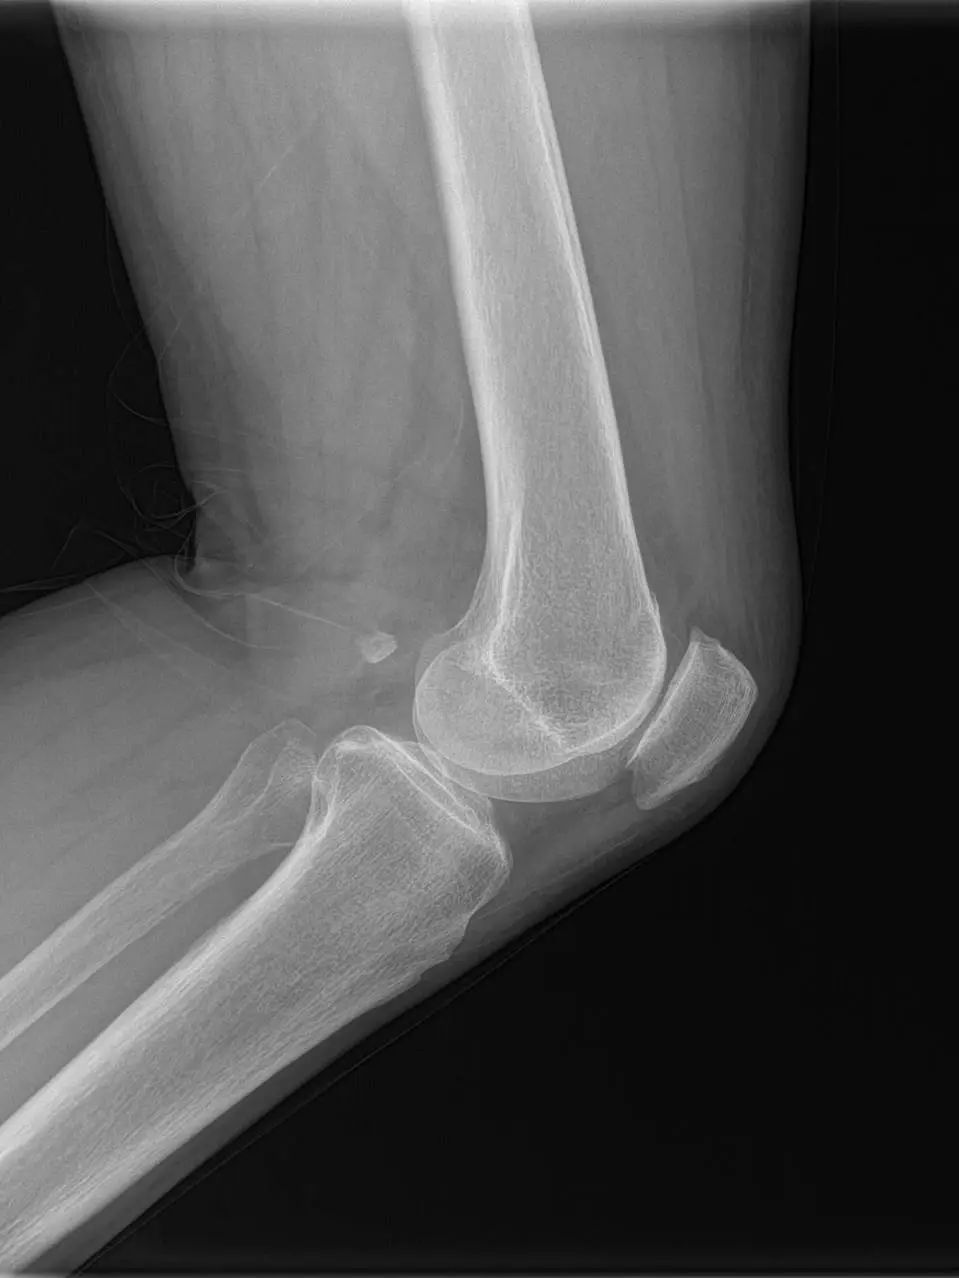

67岁的邵阿姨,双膝关节疼痛10余年,疼痛主要集中在屈伸膝关节时髌骨下。长期口服及外用药物治疗效果欠佳,反复加重,双膝的x线检查提示主要为髌股关节的退行性骨关节炎。程飚主任结合患者症状,影像学结果,体格检查,发现邵阿姨主要问题集中在髌股关节,膝关节间隙,内外侧髁,胫骨平台均可,为解决邵阿姨痛苦,尽可能保留关节,程飚主任决定对邵阿姨进行双侧膝关节的髌股关节表面置换,截骨量较少,邵阿姨第二天就能下地活动了,屈伸关节也不痛了,对手术疗效表示非常的满意。